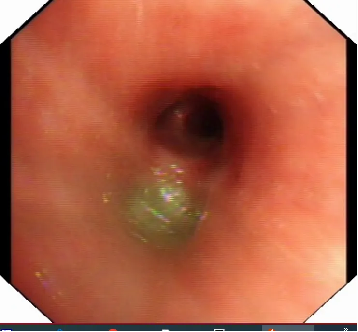

3. 胸部CT表现:

1)支气管壁增厚:这是支原体肺炎的一个常见CT表现,表现为沿支气管分布的增厚。

2)树芽征:这是由于细支气管和肺泡的炎症导致的,表现为CT影像上的细小、分支状的阴影。